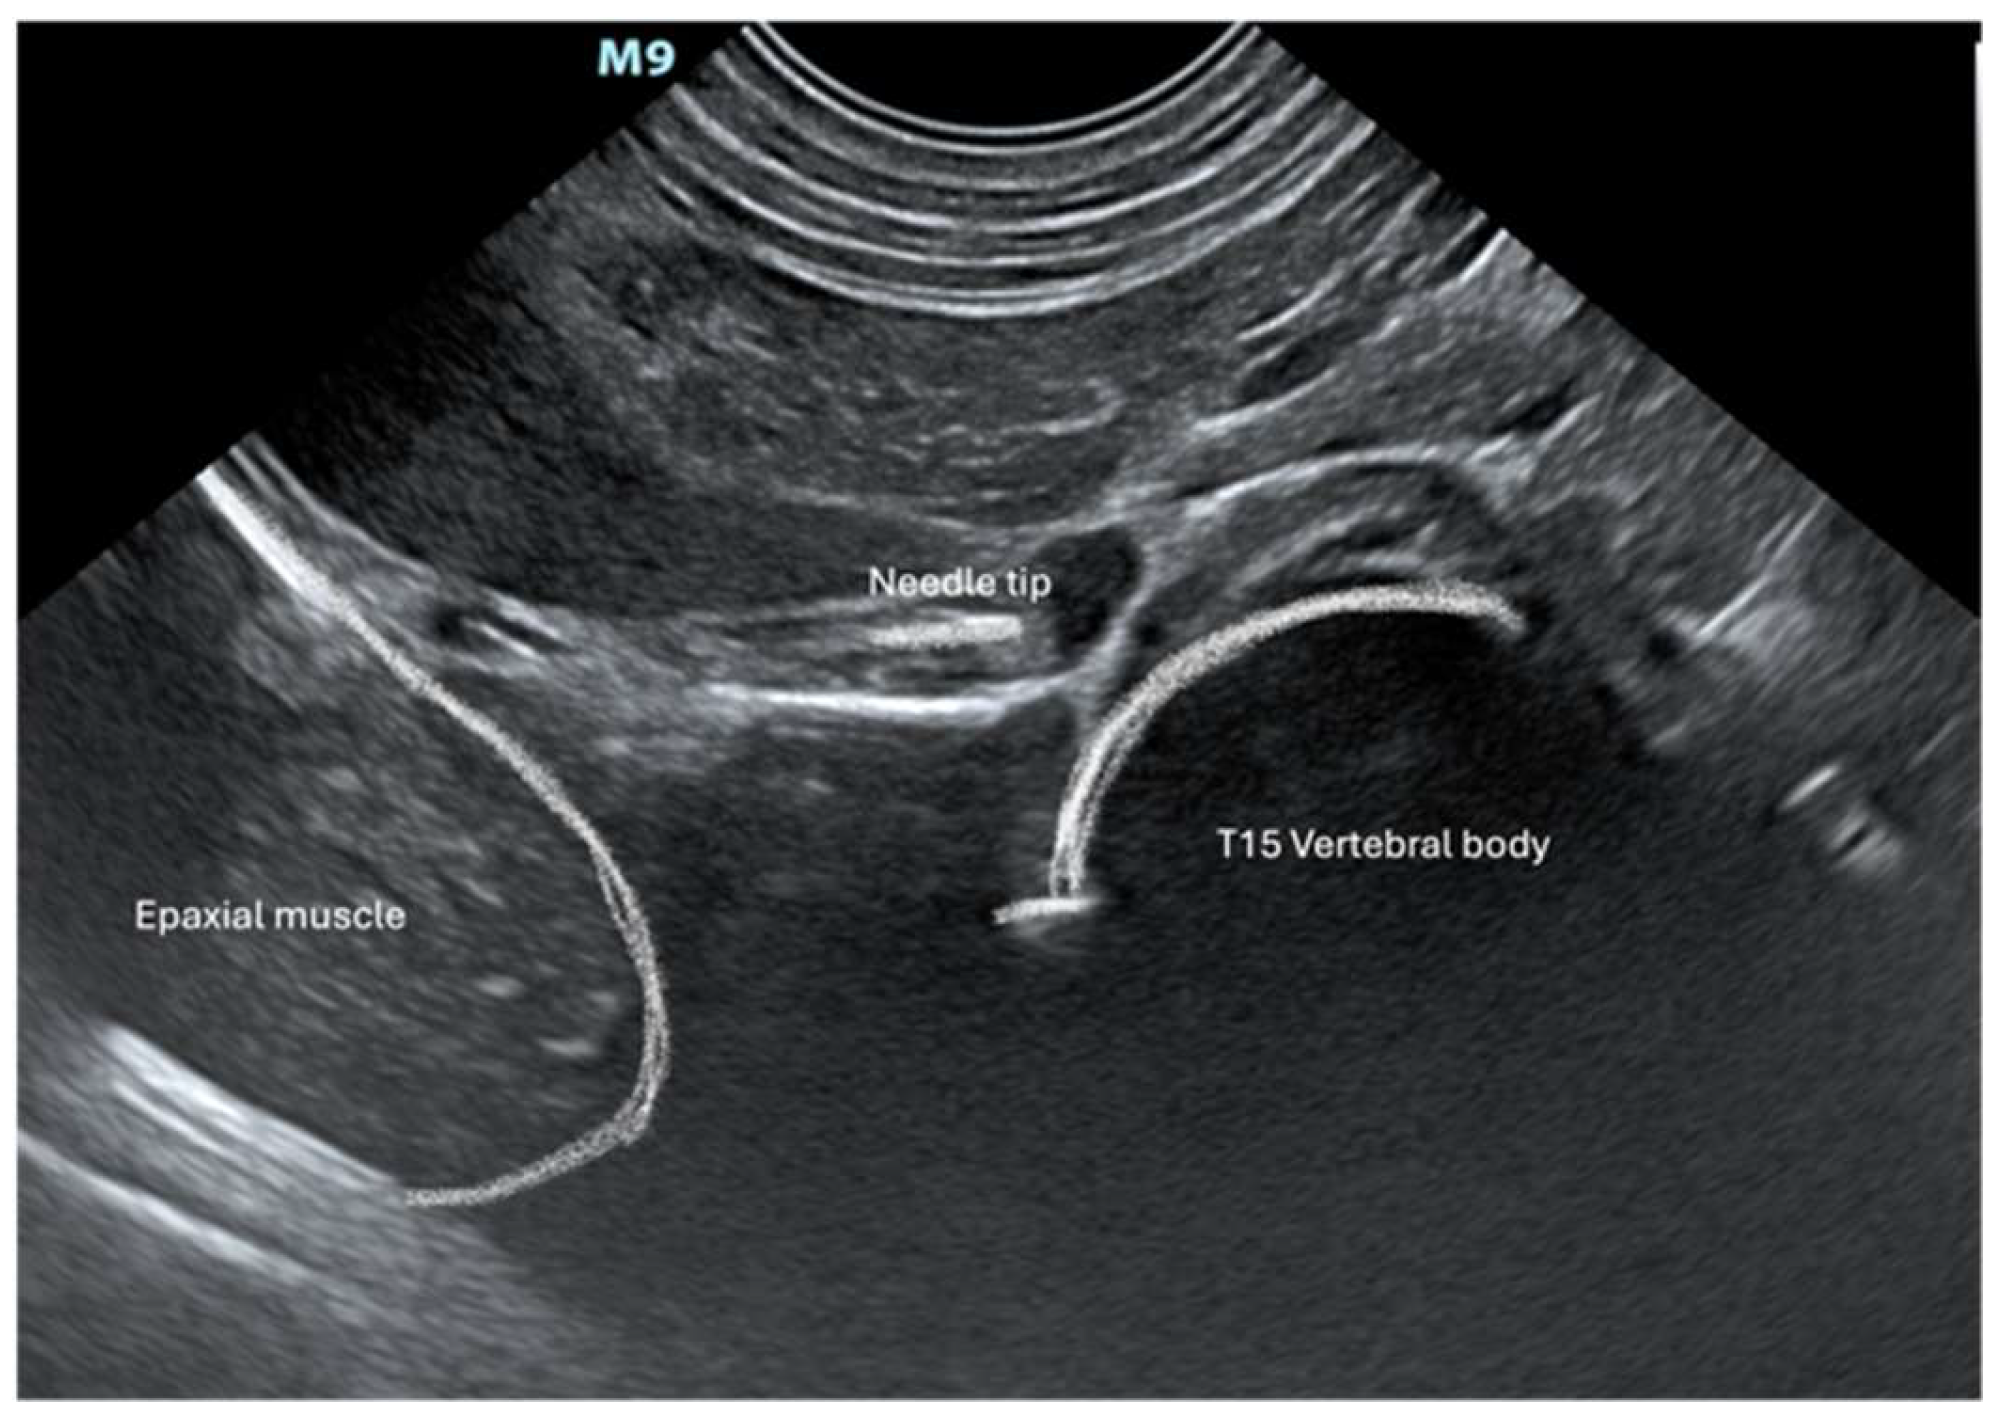

2.3. Ultrasound Approach to CP

3.1. Gross Anatomical Description and Ultrasonographic Technique